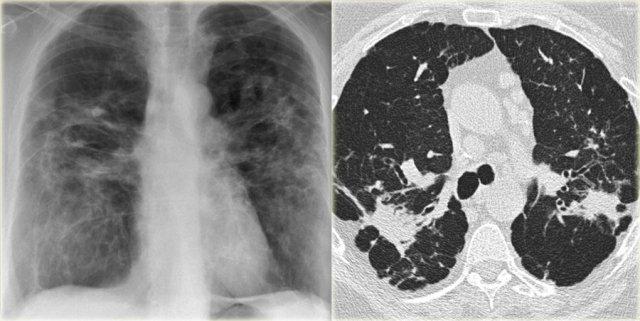

Đây là phim X-quang ngực thẳng với kiểu hình ảnh dạng lưới ở đáy phổi.

Kiểu hình ảnh này ban đầu được quy cho suy tim sung huyết mạn tính, nhưng vẫn tồn tại trên các phim X-quang ngực thẳng theo dõi dù đã điều trị.

HRCT cho thấy tổ ong hóa.

Đây là một trường hợp khác.

Phim X-quang ngực thẳng cho thấy kiểu hình ảnh mô kẽ dạng lưới với ưu thế ở đáy phổi.

HRCT cho thấy tổ ong hóa và giãn phế quản do co kéo.